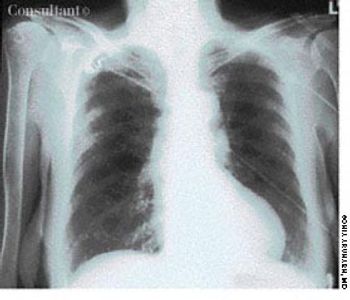

A 40-year-old man, originally an Ohio resident, underwent a chest x-ray study during medical clearance following surgery to repair a hernia. Although the patient had no pulmonary symptoms, the film showed multiple small, punctate calcifications in both lung fields.